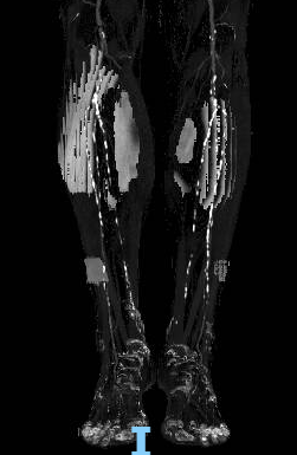

步进造影配合血管腔内超声诊断导管提示:股浅动脉全程、腘动脉、胫腓干动脉血流通畅,未见明显夹层、造影剂外溢,远端未见栓塞,膝下动脉如前。

腘动脉压力:90mmHg,比值0.73(原比值 0.54)

足背动脉压力85mmHg,比值0.69(原比值 0.45)

腘动脉压力:120mmHg,比值0.98 (原比值 0.65)

胫后动脉压力:118mmHg,比值0.96(原比值 0.54)

足背动脉压力:115mmHg,比值0.93(原比值 0.59)